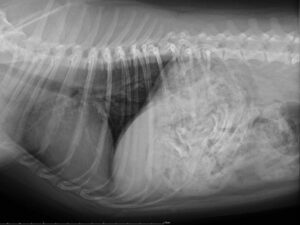

(レントゲン写真から、誤食した骨がどこにあるのか、本当に食べたのか確認することができます)

↑この子は1本丸ごと胃の中に入っています。

↑この子は胃の中がチキンの骨でいっぱいです。